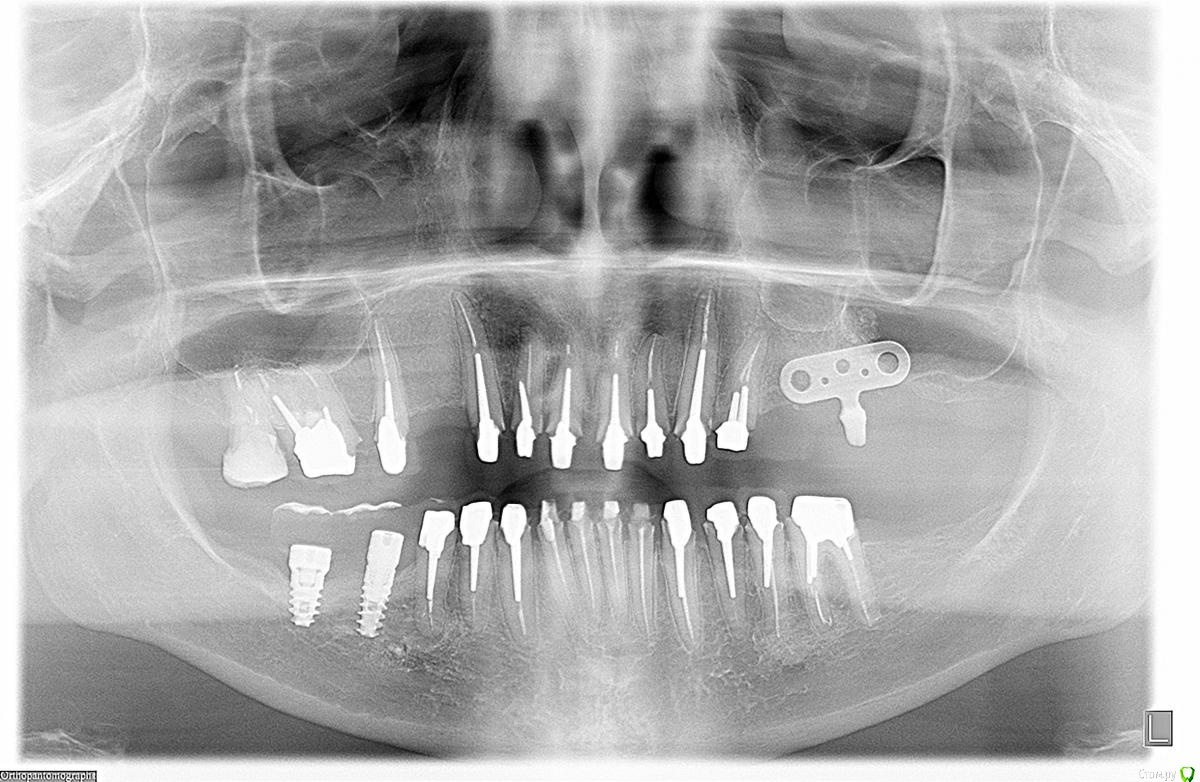

an_ver Опубликовано 1 мая, 2015 Поделиться Опубликовано 1 мая, 2015 (изменено) Обратилась пациентка, ходит с временными уже 1-1,5..что то шлифовали, что то меняли...не может привыкнуть((. Из того что увидел...гиперемия слизистой десны, слегда синюшность,сосочки раздавлены,акриловые временные (Синма) наверное.Сделали орто..и опа! Шедевр бюджета! Все ПУЛЬПИРОВАЛИ, впердолили вкладки и больше всего убила пластина....сеогодня придет...сфотаю выложу...надо как то девушке помочь. Изменено 1 мая, 2015 пользователем an_ver Ссылка на комментарий

an_ver Опубликовано 1 мая, 2015 Автор Поделиться Опубликовано 1 мая, 2015 Времяши на формиках. Уступы километр .. Печаль. Фото кидай и моделиДа уж...моделей еще нет.Сегодня только фото будет.Прилегание фкладок и направление ножек вкладок совсем в ступор ввели...блин как можно мимо захренячить...иного слова нет....ну и запил...думаю пипец там Ссылка на комментарий

kriokov Опубликовано 1 мая, 2015 Поделиться Опубликовано 1 мая, 2015 запил дебильный. Надо смотреть фотки, может за счет хирургического удлинения коронковой части выйти из положения можно , если глубоко под десну не сгнило. Пародонтита то нет. Судя по всему рукотворные там проблемы с десной .Пластина сстоит как вкопанная? Ссылка на комментарий

diesel87 Опубликовано 1 мая, 2015 Поделиться Опубликовано 1 мая, 2015 Про ортопедию не скажу, есть конечно явные косяки, что даже мне видно, но пластина убила...док сэкономить решил деньги пациента на хирургии и снять с нее больше на ортопедии? Сколько годков барышне? Ждем фото. Ссылка на комментарий

johniola Опубликовано 1 мая, 2015 Поделиться Опубликовано 1 мая, 2015 Ну нифига себе,даже я так не смогу.Там надо десну поднимать,и наверно кость тоже.Вкладки думаю бы не вынимал,только хуже будет,хотя инфы мало.На 12 до перфы чуть недотянул.имхо Ссылка на комментарий

gum Опубликовано 2 мая, 2015 Поделиться Опубликовано 2 мая, 2015 Нет извлекать вкладки очень рискованно, длинные штифты, высокий риск истончение стенок корней. А пластиночный имплантат тот же хирург ставил или это отголосок прошлого? Ссылка на комментарий

an_ver Опубликовано 2 мая, 2015 Автор Поделиться Опубликовано 2 мая, 2015 Нет извлекать вкладки очень рискованно, длинные штифты, высокий риск истончение стенок корней. А пластиночный имплантат тот же хирург ставил или это отголосок прошлого?Все тот же Ссылка на комментарий

an_ver Опубликовано 2 мая, 2015 Автор Поделиться Опубликовано 2 мая, 2015 Вот фото Ссылка на комментарий

an_ver Опубликовано 4 мая, 2015 Автор Поделиться Опубликовано 4 мая, 2015 Да,пластина стоит мертво...со слов пациентки еще синус делали Ссылка на комментарий